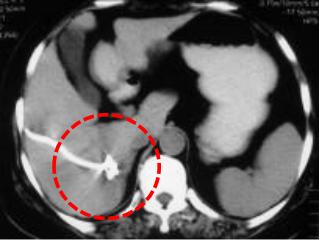

原发性肝癌依赖人体血液供应不断生长,介入治疗可以经肝动脉注入栓塞剂,阻断病变的血液供应,使肿瘤缺乏生长所需的营养,进而抑制肝癌的生长。